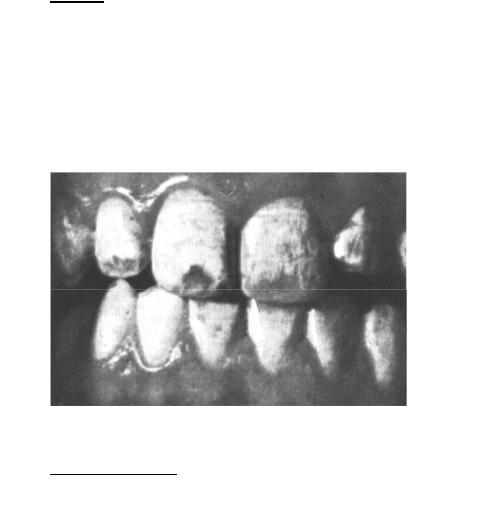

Клиника флюороза зависит от тяжести проявлений, поэтому выделяют следующие формы: пятнистую, штриховую, меловидно-крапчатую, эрозивную и деструктивную (Патрикеев В.К., 1956). Последние две формы протекают с потерей тканей зуба. Пятна и полости могут быть меловидного цвета или пигментированными: жёлтыми, коричневыми. При незначительном превышении фтора поражаются только резцы, при большом - все зубы

(рис. 8).

Больные предъявляют жалобы на косметический дефект, субъективные ощущения отсутствуют. При штриховой и пятнистой форме эмаль гладкая, блестящая; при меловидно-крапчатой форме она теряет блеск и прозрачность. Эрозивная и деструктивная формы проявляются в виде уча-

14

стков дефекта твёрдых тканей зуба, выражено стирание эмали и дентина, может наблюдаться отлом тканей вследствие их хрупкости.

Рис. 8: Флюороз